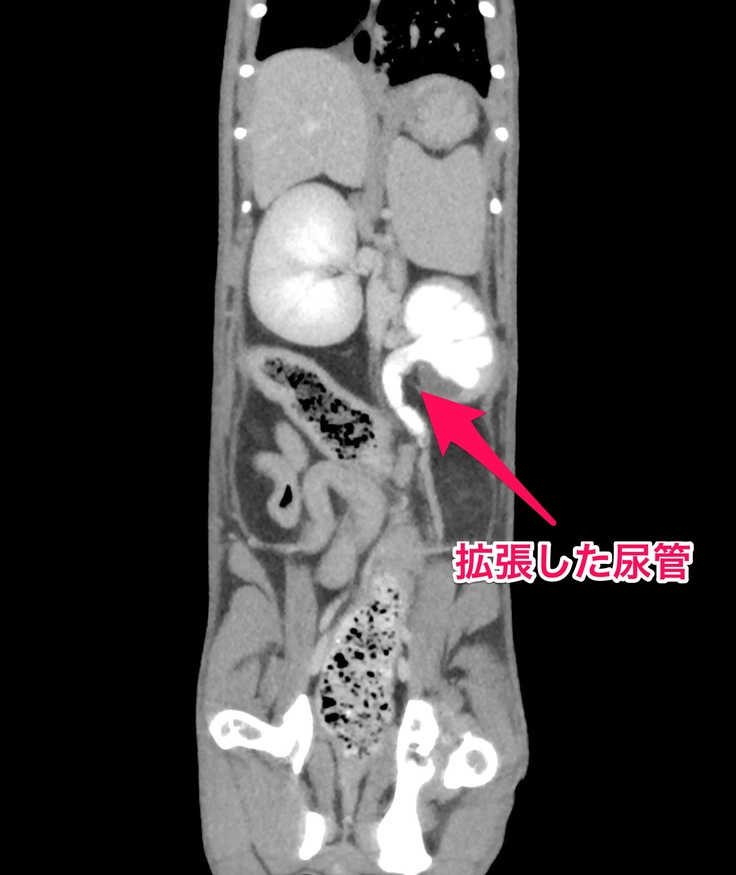

●左側の腎臓と腎盂が肥大して、ほとんど機能していない状態。(右側の腎臓と腎盂は正常)

ヨッチャンの腎臓の手術の内容ですがエコー検査で尿管が何かしらの原因で細くなっており、

①尿管結石になっている場合は石を取り除く手術

②細くなっている尿管の場所が腎臓に近い場合は尿管を切って、腎臓と膀胱をつなぐ手術

③細くなっている尿管の場所が膀胱に近い場合はSUBシステムを用いた腎臓-膀胱バイパス手術

CT検査とエコー検査の結果、ヨッちゃんの尿管が細くなっている原因は尿管結石ではなく①の手術は対象外となりました。尿管が細くなっている原因は先天性のものなのか後天性のものなのかは分からないけど、比較的腎臓に近い場所から尿管が細くなっているから②の手術で対応出来そうということで、たちまち腎臓と膀胱をつなぐ手術をしてもらうことになりました。

ただ、②の手術は成功しても術後にまた尿管が詰まってしまう場合には、③のSUBシステムを用いた腎臓-膀胱バイパス手術を再度受けてもらうことになることと、③の手術をした場合は2か月に1回バイパスの洗浄が必要になるので通院してもらうことになりますと説明を受けているので、今後、ヨッちゃんの経過次第では③の手術を受けることがあるかもしれません。